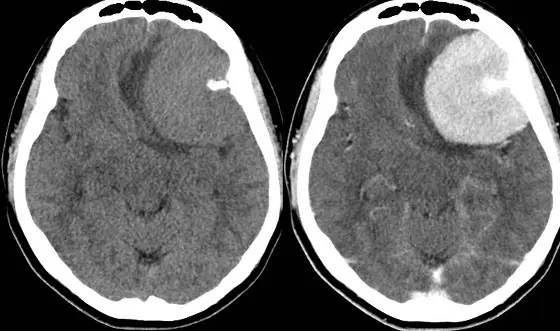

27.頭部 CT 的影像如下圖,下列何者為最有可能之診斷?

本題提供兩張橫切面(axial)的頭部 CT 影像:

- 左圖(無對比劑 CT,Non-contrast CT):

- 於左側額葉可見一巨大的「軸外(extra-axial)」腫塊。該腫塊將正常的腦皮質向內推擠(白質塌陷徵,white matter buckling),並以廣基底(broad-based)附著於左側顱骨內側的硬腦膜上。

- 腫塊主體的密度與正常腦皮質相近,呈現「等密度至稍高密度(isodense to slightly hyperdense)」。

- 腫瘤外側邊緣可見一極高亮度的緻密病灶,為典型的「鈣化(calcification)」。

- 腫瘤周圍伴隨大片低密度的「血管性水腫(vasogenic edema)」,並造成嚴重的「腫塊效應(mass effect)」,明顯壓迫左側側腦室,導致中線結構向右側偏移(midline shift)。

- 右圖(對比劑強化 CT,Contrast-enhanced CT)